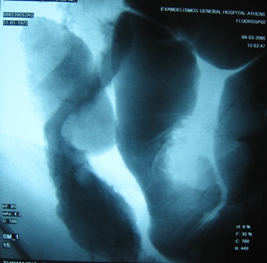

Στους ίδιους ασθενείς η εντερόκλυση μπορεί να αναδείξει ανάλογα ευρήματα με την ενδοσκοπική κάψουλα (εικόνες 36-43) ή να είναι φυσιολογική (εικόνες 44-48).

36  37

Εικόνες 36, 37. Ο ίδιος ασθενής με τις εικόνες 15, 16. Εικόνα πλακόστρωτου με στένωση και παρουσία        βαθιάς εξέλκωσης του βλεννογόνου